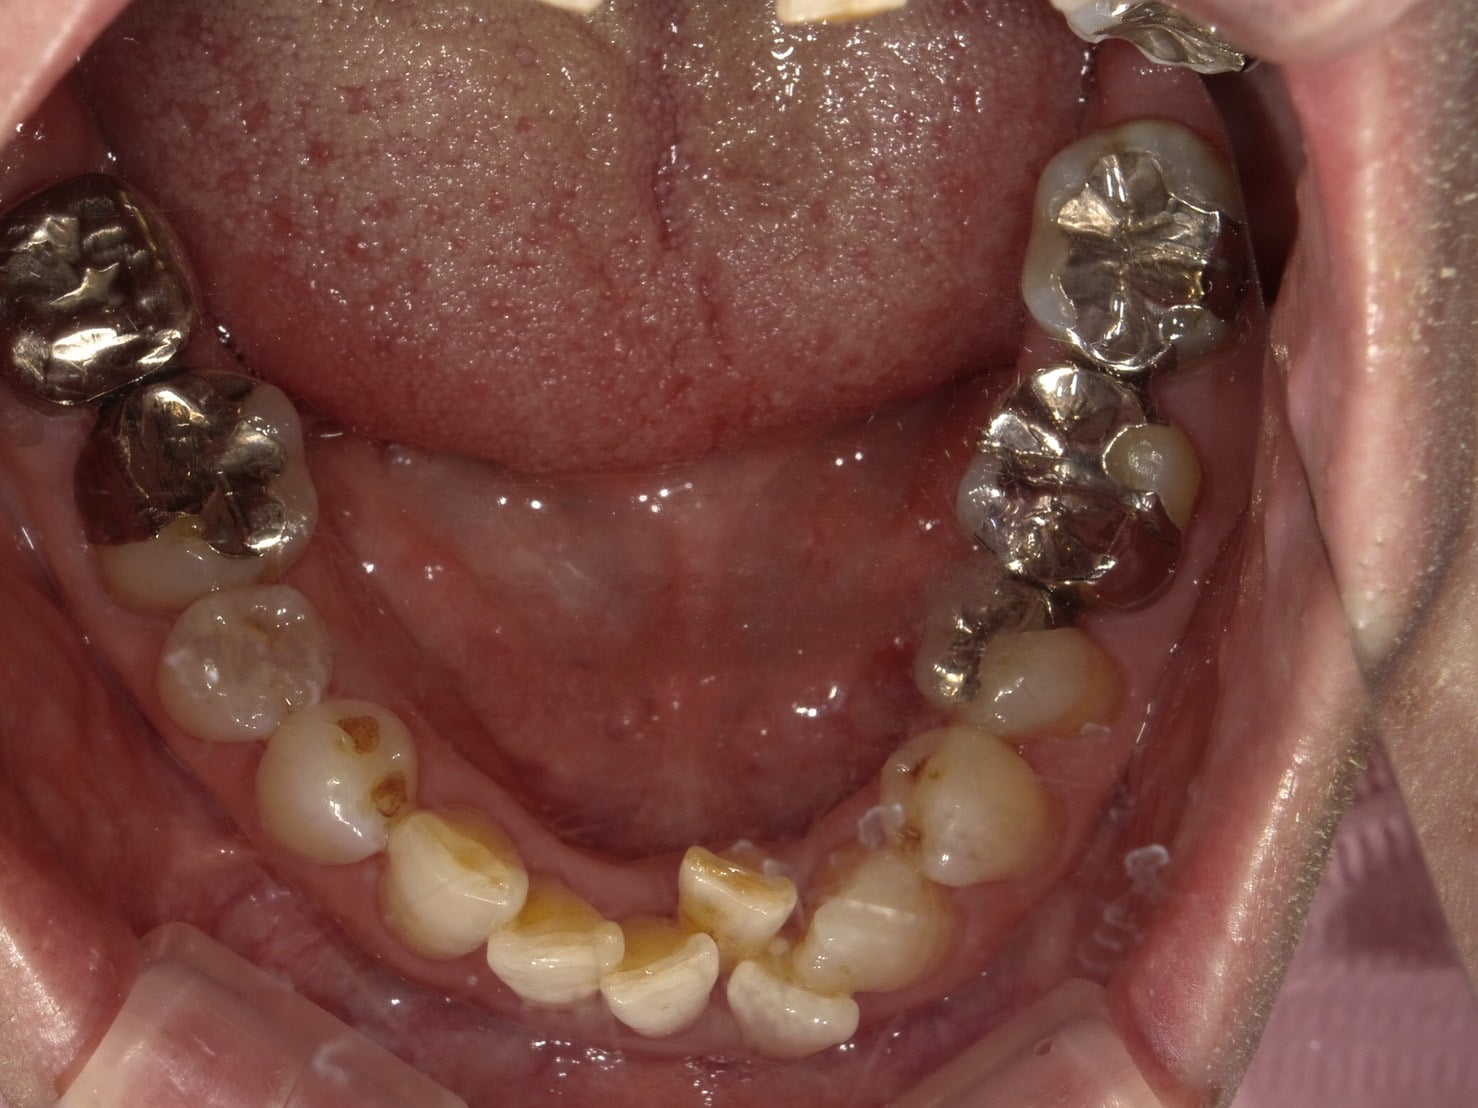

• お悩み

他院で矯正相談したら 抜歯しての矯正になると言われた

年齢

36歳/男性

治療期間

2年3ヶ月

施術説明

歯並びや噛み合わせの不全をアライナー型矯正装置を装着し、歯並びや噛み合わせを改善し適切な状態にする治療です。

副作用

装着したまま糖分の入った飲料を取ると、虫歯を発症しやすくなります。正しい装着方法で1日20時間以上使用しないと、目標とする治療結果を得れないことがあるため、きちんとした自己管理が必要になります。

他院で矯正相談したら

抜歯しての矯正になると

言われた